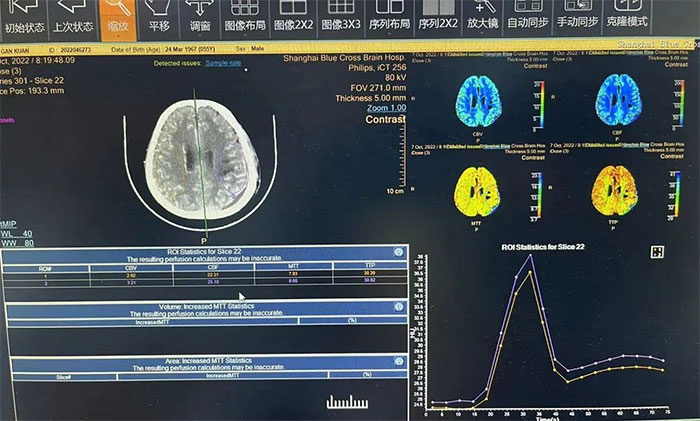

▲ 术后查CTP,左侧大脑灌注明显改善

术后,在6A病区医护团队的精心治疗和护理下,苏先生恢复情况良好。再经系统的肢体康复训练,不到半个月,右侧肢体的运动功能也基本恢复了正常。